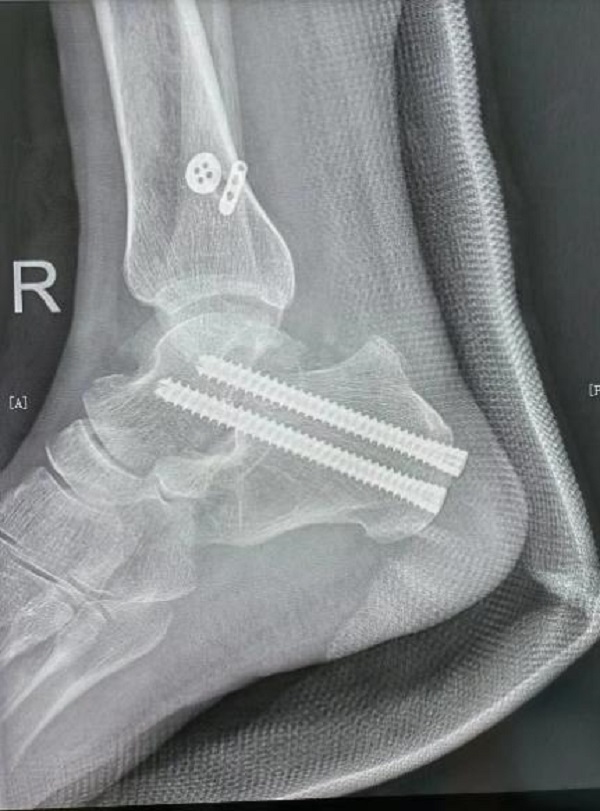

术后影像学资料